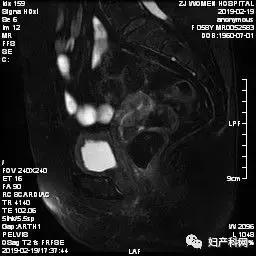

2019.2.19盆腔MRI平扫+增强(图像如下):子宫肌瘤,内膜信号欠均匀。